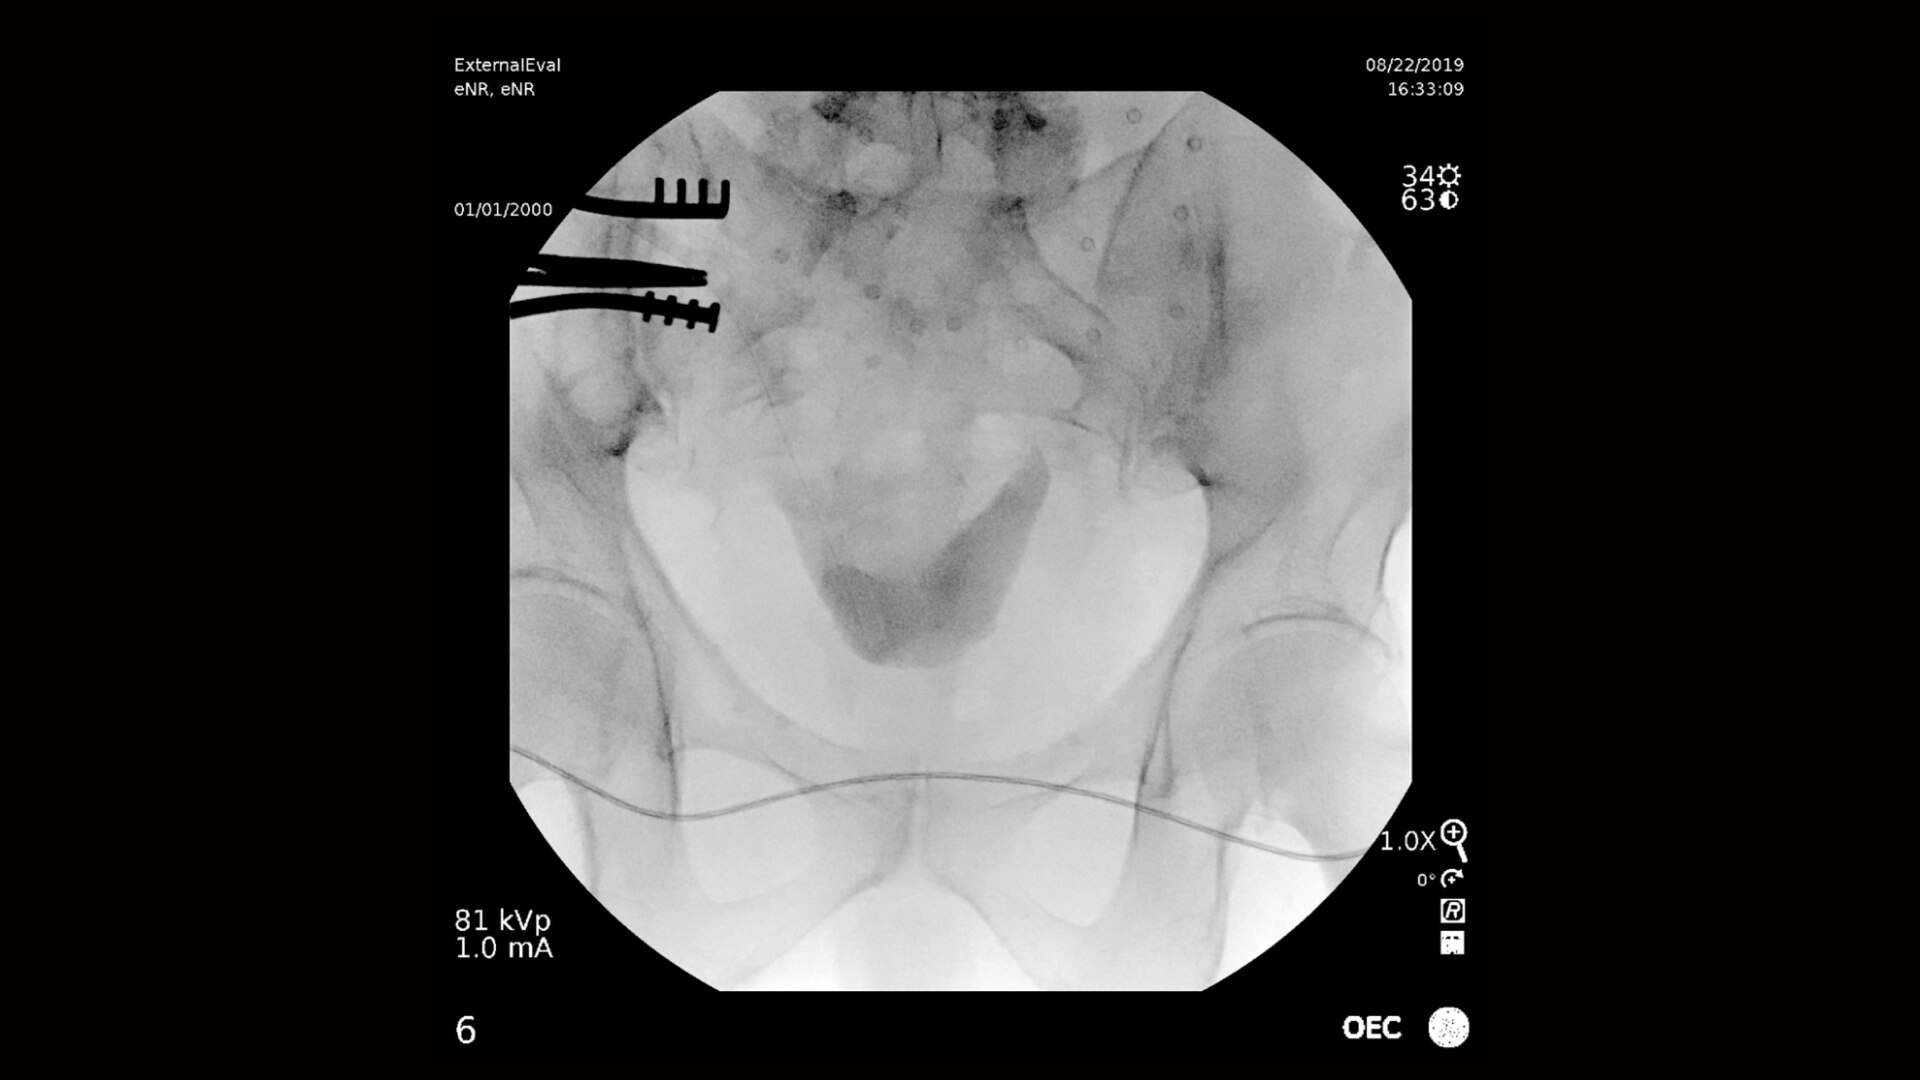

Четкая визуализация всего мочевыводящего пути: от почек до мочевого пузыря. С-дуги OEC обеспечивают потрясающее качество изображений, позволяя интервенционистам легко анализировать мелкие детали мочевыводящих путей, такие как урологические полости. Четкий дисплей с большим полем обзора обеспечивает полную визуализацию без необходимости изменения положения С-дуги, что упрощает рабочий процесс.

Передача информации от детектора на дисплей UHD обеспечивает потрясающее качество изображений, в т. ч. визуализацию дренажных трубок низкой плотности и тонких щеточек для биопсии с отображением деталей в масштабе 1 к 1.

Профиль предустановки General HD оптимизируется для представления высококонтрастных изображений с улучшенными краями, что обеспечивает качественную визуализацию мелких деталей, таких как камни в протоке поджелудочной железы.